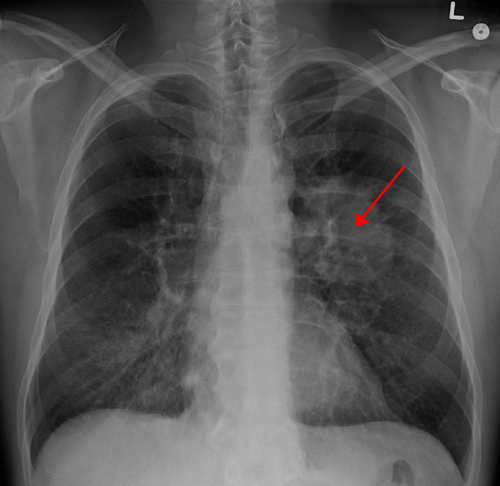

James Heilman, MD · CC BY-SA 3.0 · source

DiagnosisChest radiography, Computed tomography, Bronchoscopy

Initial evaluation typically uses chest radiography and high-resolution Computed tomography scanning; positron emission tomography with radiotracers informs metabolic activity and staging, often performed at facilities like Johns Hopkins Hospital and Stanford Health Care. Tissue diagnosis relies on bronchoscopy, CT-guided biopsy, or surgical resection for histopathology and molecular testing in certified laboratories associated with institutions such as FDA-regulated centers. Ancillary testing includes immunohistochemistry panels and next-generation sequencing to detect actionable mutations described in trials published by groups like American Society of Clinical Oncology.